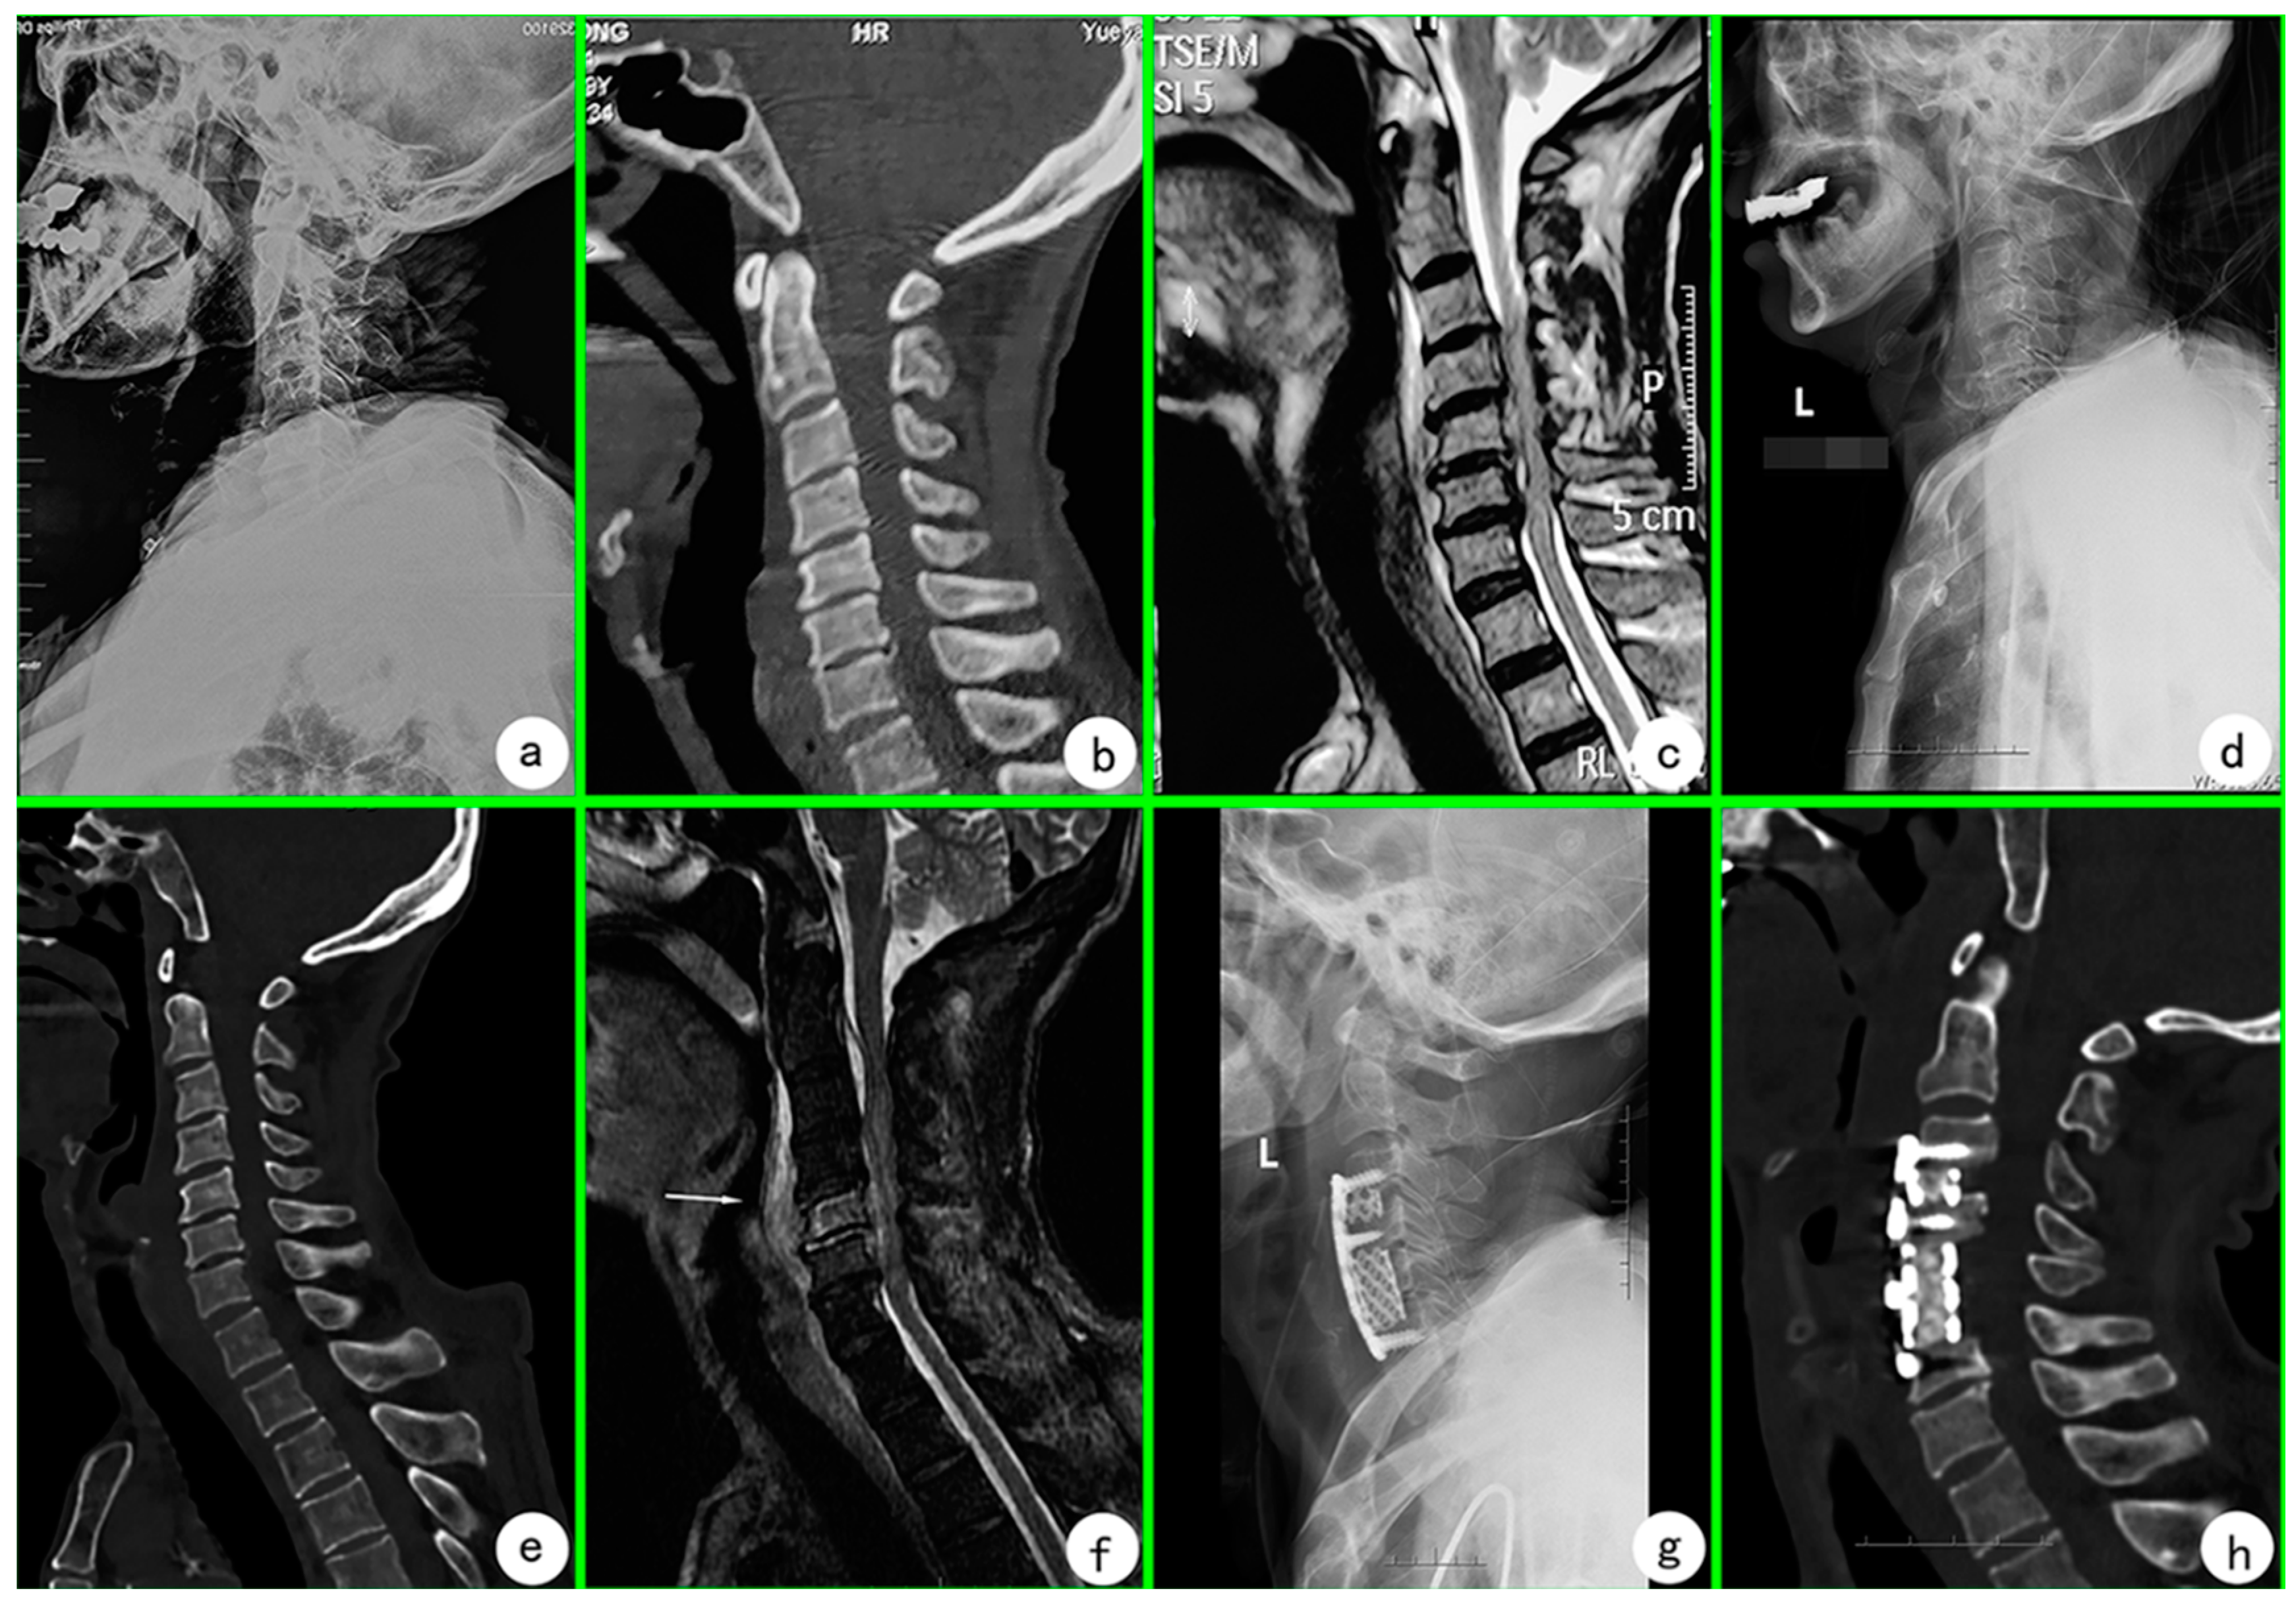

2. Case Presentation